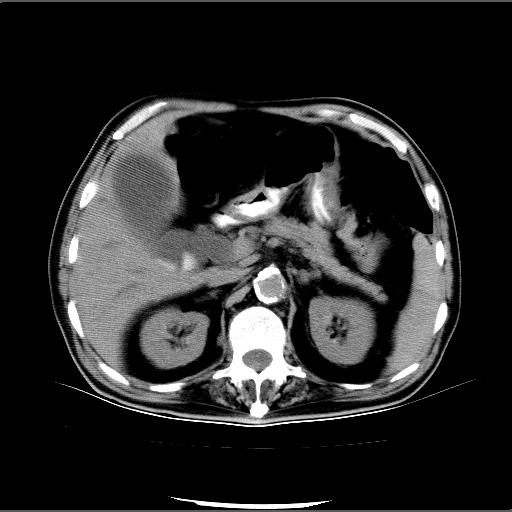

患者男82岁,黄染,发热10天,无腹痛。

1胆总管下端结石伴肝内外胆管扩张;2胆囊颈部结石伴胆囊积液

胆囊多发结石,胆囊积液;胆总管中下段结石,中上段扩张。

胆总管下段结石伴胆道系统扩张;胆囊炎伴胆囊结石.

有时胆总管下段结石的密度并不是均匀的高密度,而是以高密度为主的伴中心等密度的混合物,这与胆道结石的多样性有关,少数时候诊断困难时应结合临床病史,症状等,还有增强扫描都可以帮助明确诊断!!常与胆道蛔虫伴钙化鉴别!

1、胆总管壶腹部结石并胆总管、胆囊及肝内胆管扩张。2、胆囊多发结石。3、两下胸膜局限性增厚。4、胃体部大弯侧胃壁稍厚,建议:多量饮水后增强ct扫描除外占位性病变。

此病例有结果了:患者术后为:胆总管下段结石伴胆道系统扩张;胆囊炎伴胆囊结石。

各位战友分析的都很正确,是一个典型的病例。